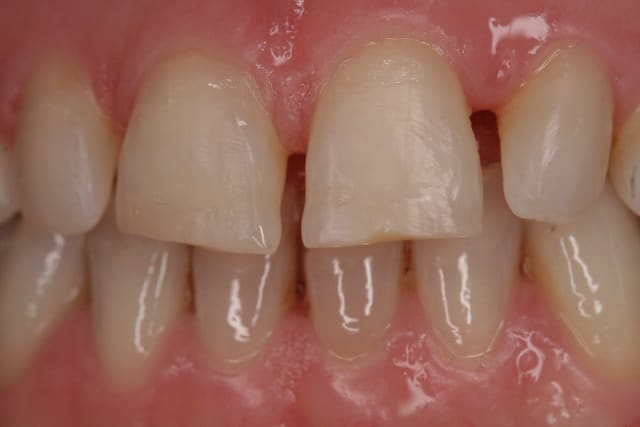

essayage, et comme on peut le voir sur la première photo, c'est bizarement long par rapport au provisoire ...

pourtant le prothésiste avait un alginate des mocks-up

j'ai mis du sealtemp et essayé tout ça, c'est trop long

par contre, je me dis que je suis resté trop supra-gingival sur mes préparations, ça se voit trop, même si la patiente découvre peu, elle découvre un peu et j'aurais du aller plus juxta.

Zooom bjj8ay - Eugenol